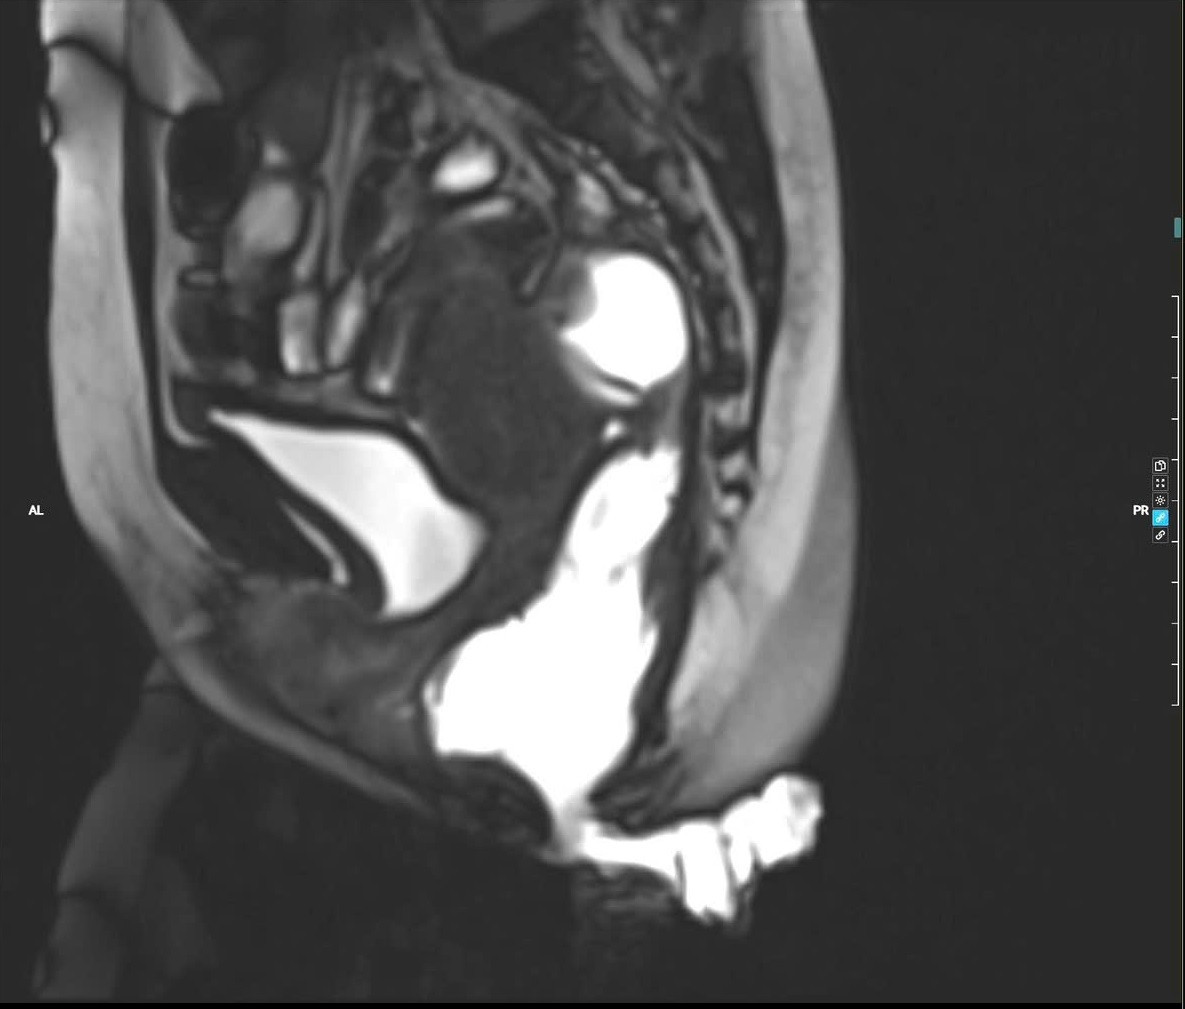

Hình ảnh chụp cộng hưởng từ động tống phân cho thấy hình ảnh túi sa thành trước trực tràng kiểu túi, sa nhẹ bàng quang - Ảnh BVCC

Người bệnh đã đến Bệnh viện TWQĐ 108 khám và được chỉ định thực hiện các xét nghiệm như chụp cộng hưởng từ động tống phân (Defecography MRI) để đánh giá toàn diện. Bệnh nhân được chẩn đoán: Táo bón do sa thành trước trực tràng kiểu túi độ III; trĩ hỗn hợp độ IV; nứt kẽ hậu môn mạn tính sau tiêm xơ trĩ 5 tháng; són tiểu mức độ nhẹ.